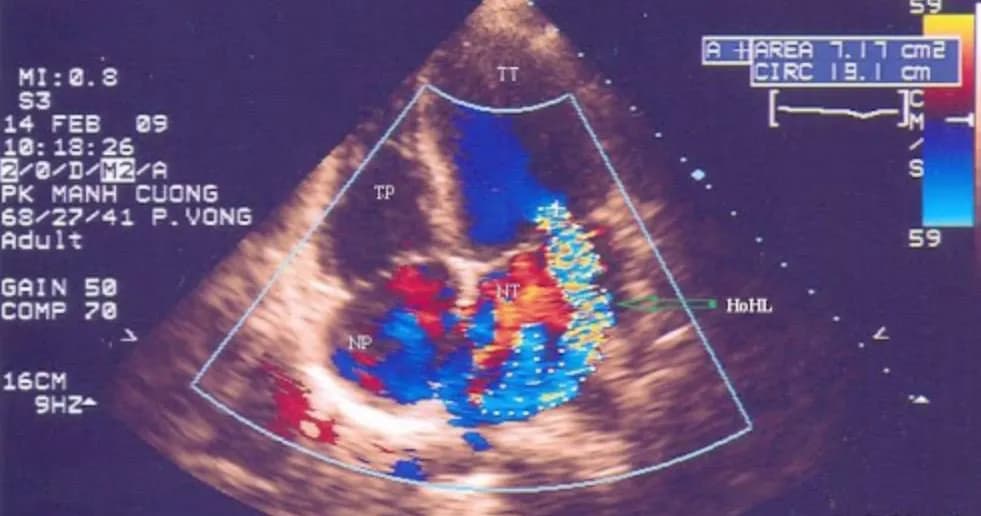

Siêu âm tim hở van 2 lá bằng phương pháp siêu âm Doppler màu được sử dụng rộng rãi để chẩn đoán xác định và đánh giá mức độ hở van lá. Hở van 2 lá trên siêu âm Doppler được chia làm 4 độ từ 1/4 đến 4/4. Hoặc cũng có thể đánh giá bằng các mức độ từ nhẹ (1+), vừa (2+), nhiều (3+) và rất nhiều (4+). Siêu âm Doppler màu giúp nhìn thấy được hình ảnh dòng màu phụt ngược về nhĩ trái. Dựa vào sự lan của dòng màu phụt ngược có thể ước tính độ hở của van 2 lá. Để đánh giá cụ thể hơn mức độ hở của van, có thể dựa vào các thông số như:

- Tỷ lệ diện tích dòng hở so với diện tích nhĩ trái.